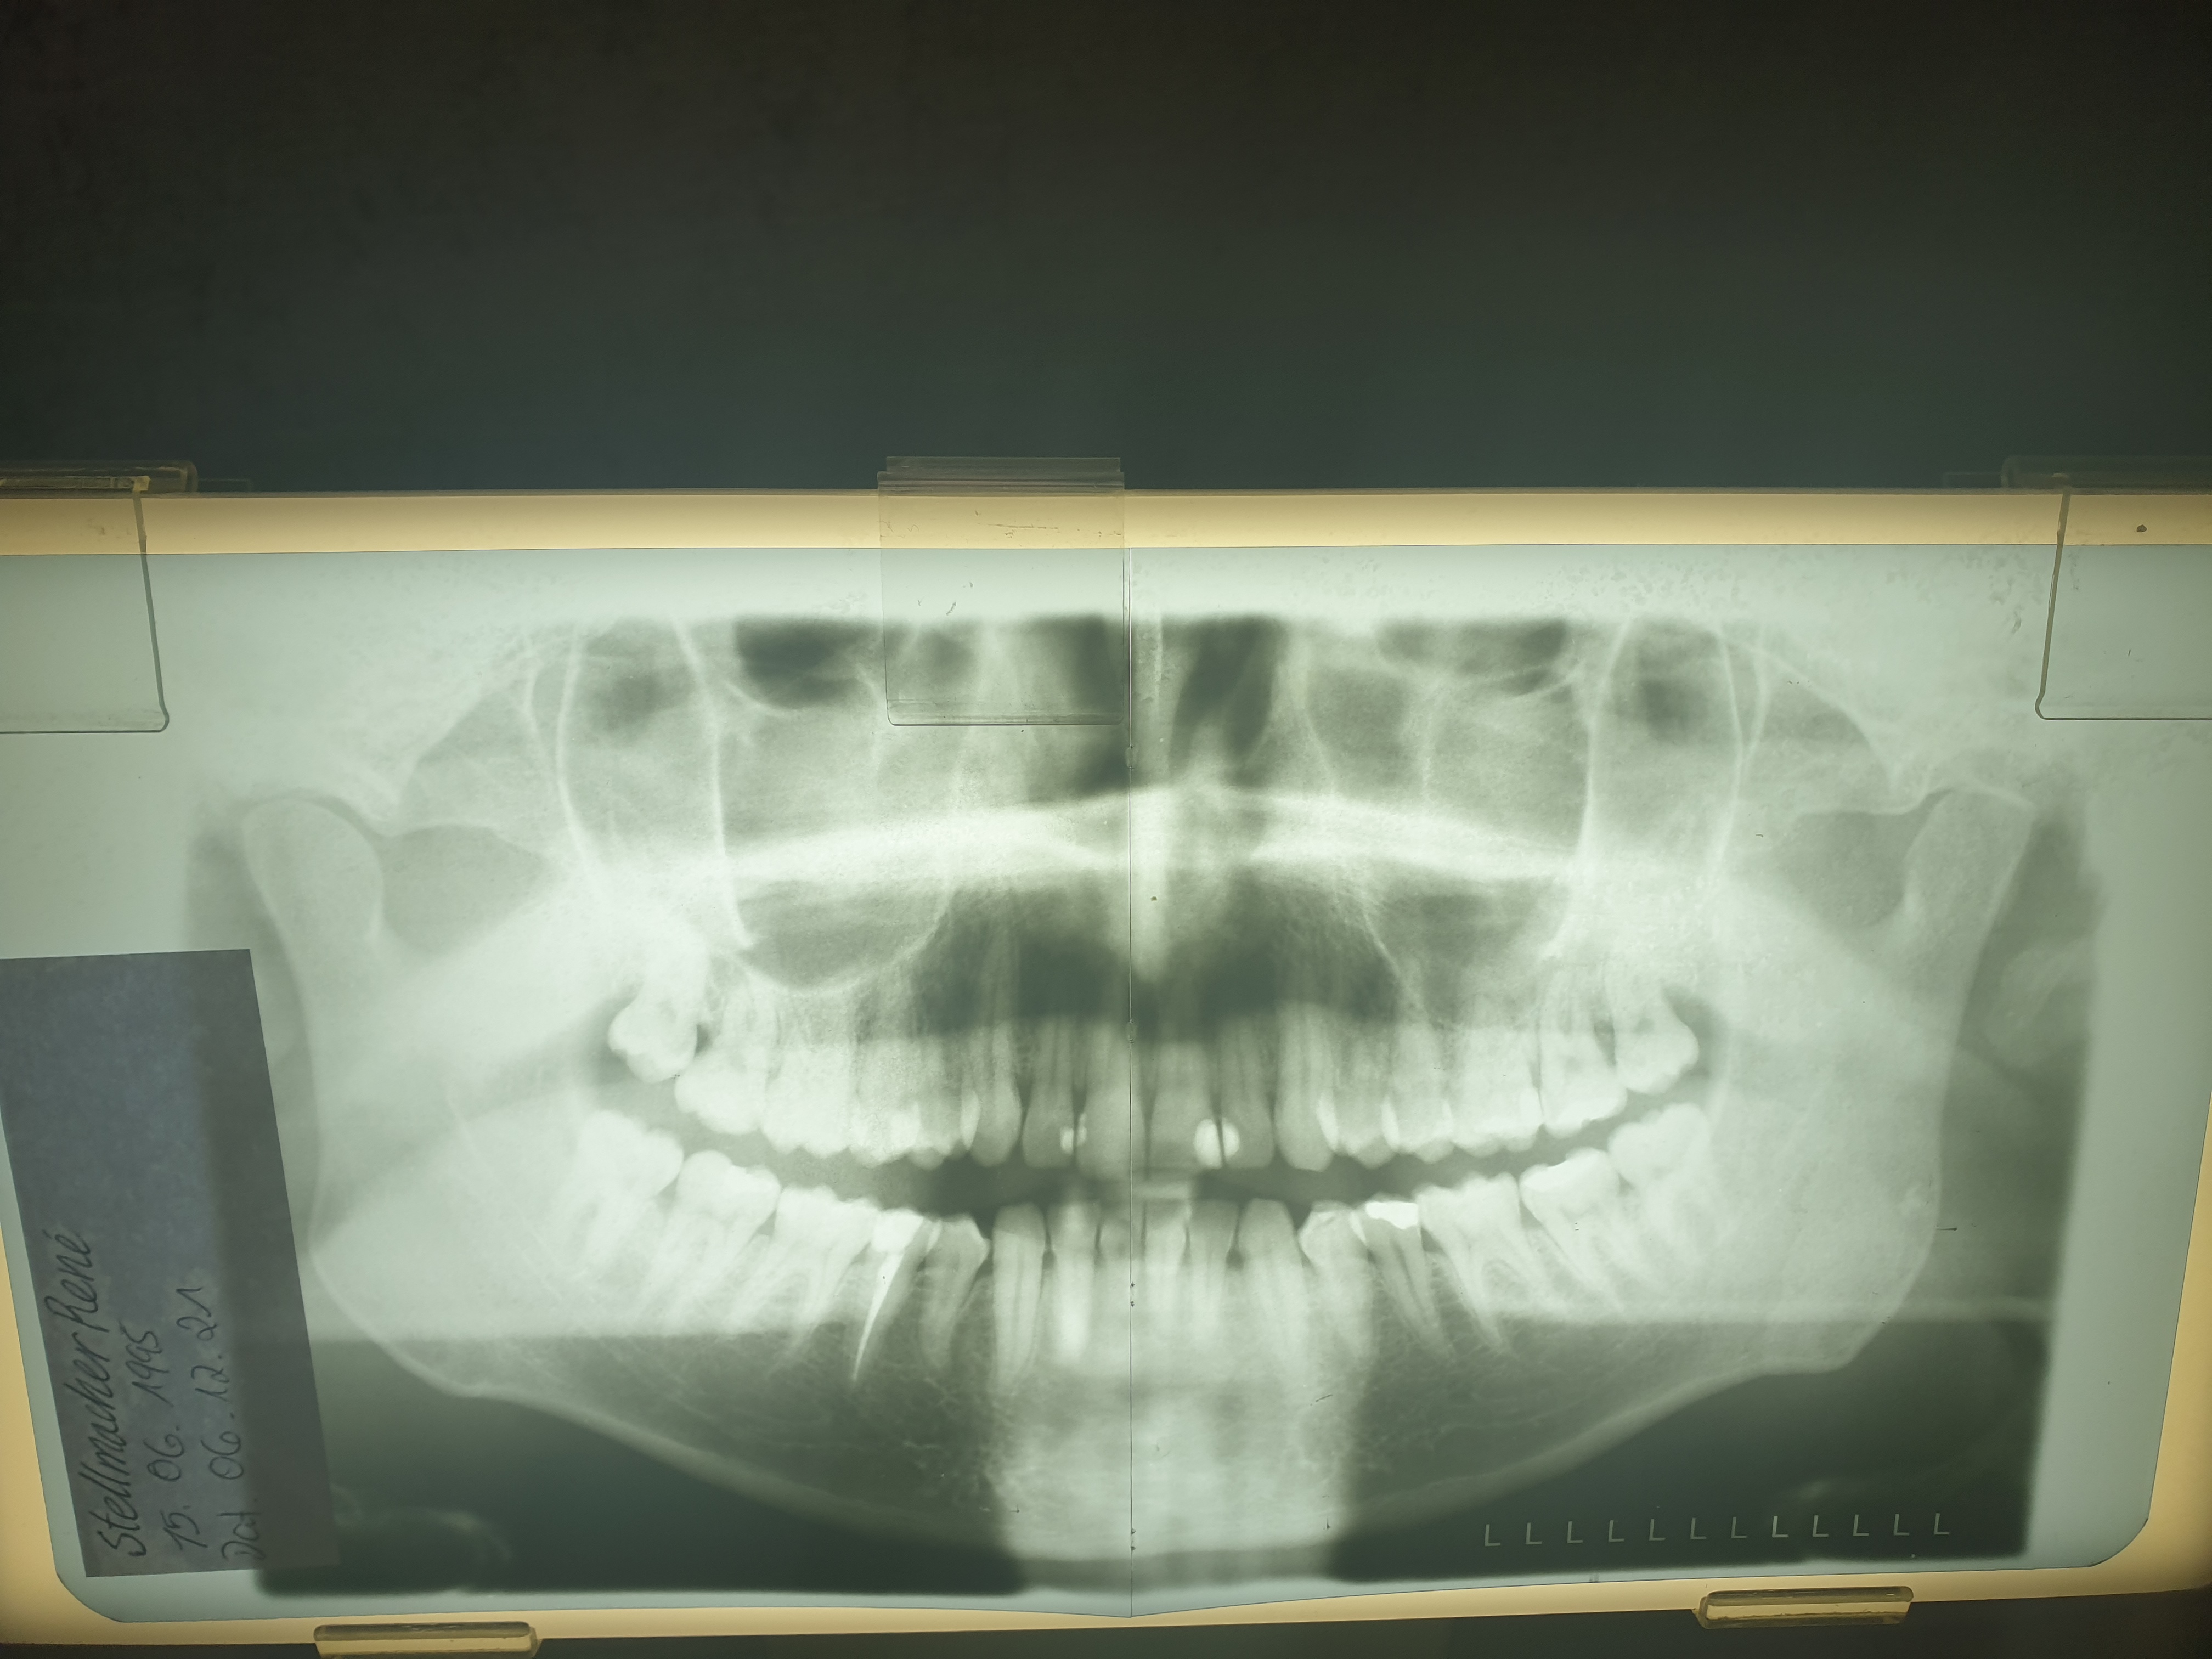

Hallo und zwar bin ich momentan echt verzweifelt wegen meines unteren kiefer gelenks ich habe vor paar monaten ein knacken beim nach vorne beugen von einem stuhl gemerkt seit dem geht nix mehr schwindel beim zu schnell gehen schluckbeschwerden mein ganzer körper knackt vor sich hin je nach bewegung tinnitus usw hab mir den atlas richten lassen am 30.12.2021 leider hat mein kiefer sich nicht begradig was soll ich nur tun ne schiene hab ich schon bringen tut sie nix und ich halte nix davon weil ich mir denke das man doch diese fehlstellung die plözlich kamm (nen knacken) das irgendwer doch mit bestimmten handgriffen den kiefer wieder in seine position bringen muss ?

Ps. Mein atlas war nach links innen verschoben kann es sein das der quervorsatz des atlas mein kiefer zwecks knackens in eine fehlstellung gezwungen hat ?

Also sollte ich spiral ct anfordern ? Oder was ist damit gemeint warum ich das lessen sollte die atlas spezialisten meinte das mein atlas jetzt richtig sitzt allerdings kommt mein kiefer anscheint nicht aus der fehlstellung

Ich hatte sonst noch nie probleme bis auf diesen einen tag wo es geknackt hat meine zahnärzten meinte zu mir das es nicht wieder zurück gehen wird hat mir aber ne schiene gegeben mit funktion was keinerlei verbesserung brachte